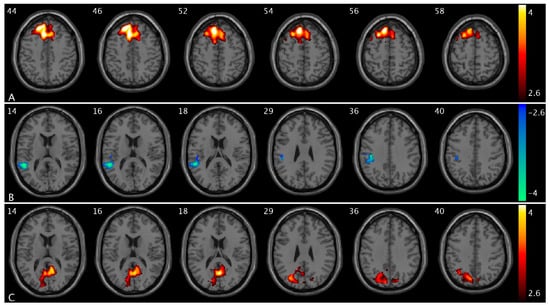

We observed altered CBF in OAB participants compared to healthy controls in different urge states. Specifically, compared to controls, OAB participants exhibited decreased CBF in the Rolandic extending to inferior frontal and orbitofrontal cortex, precuneus, supramarginal, and angular extending to inferior parietal cortex, Heschl extending to superior and middle temporal cortex, calcarine and cuneus extending to middle and superior occipital cortex, vermis, insula, thalamus, caudate, PCC, middle cingulate cortex, hippocampus, and amygdala regions in the low-urge state (Figure 4A and Figure S1A) and in the Rolandic, rectus, precentral extending to middle, superior, inferior, and orbital frontal cortex, angular/supramarginal, Heschl extending to superior temporal cortex, vermis extending to cerebellum, insula, thalamus, caudate, pallidum, amygdala, and anterior cingulate cortex (ACC) regions in the high-urge state (Figure 4B) and increased CBF in the supplementary motor extending to superior frontal and middle frontal cortex, fusiform extending to inferior temporal cortex, and ACC regions in the low-urge state (Figure 4C and Figure S1B) and in the inferior occipital regions in the high-urge state (Figure 4D). A summary of the clusters’ statistics is reported in Table S1.

We observed altered PCC FC in OAB participants compared to controls in different urge states. Specifically, OAB participants exhibited decreased PCC FC with the precentral, postcentral, and paracentral extending to inferior parietal cortex and middle cingulate regions (Figure 5A) and increased PCC FC with the calcarine, insula, putamen, and pallidum regions (Figure 5B) in the low-urge state. A summary of the clusters’ statistics is reported in Table S1.

Figure 4. Statistical maps overlaid on T1-weighted images showing altered CBF in OAB participants compared to controls in the low- and high-urge states. (A) Decreased CBF the Rolandic extending to inferior frontal, precuneus, supramarginal, and angular extending to inferior parietal cortex, Heschl extending to superior and middle temporal cortex, calcarine and cuneus extending to middle and superior occipital cortex, insula, thalamus, caudate, PCC, middle cingulate cortex (within the same slice range as in Figure 1B) in OAB participants in the low-urge state; (B) decreased CBF in the Rolandic, rectus, precentral extending to middle, superior, inferior, and orbital frontal cortex, angular/supramarginal, Heschl extending to superior temporal cortex, vermis extending to cerebellum, insula, thalamus, caudate, pallidum, amygdala, and anterior cingulate cortex (ACC) regions in OAB participants in the high-urge state; (C) increased CBF in the supplementary motor extending to superior frontal and middle frontal cortex (within the same slice range as in Figure 1A) in OAB participants in the low-urge state; and (D) increased CBF in the inferior occipital regions in OAB participants in the high-urge state compared to healthy controls. Additional decreased CBF and increased CBF regions in OAB participants in the low-urge state are shown in Figures S1A and S1B, respectively. The numbers in the top left corner of the MRI images indicate the z-coordinate (in mm) in the MNI space. The color bars represent t-values.

Figure 5. Statistical maps overlaid on T1-weighted images showing altered PCC FC in OAB participants compared to controls at different urge states. (A) Decreased PCC FC with the precentral, postcentral, and paracentral extending to inferior parietal cortex and middle cingulate regions and (B) increased PCC FC with the calcarine, insula, putamen, and pallidum regions in OAB participants compared to healthy controls in the low-urge state. The numbers in the top left corner of the MRI images indicate the z-coordinate (in mm) in the MNI space. The color bars represent t-values.